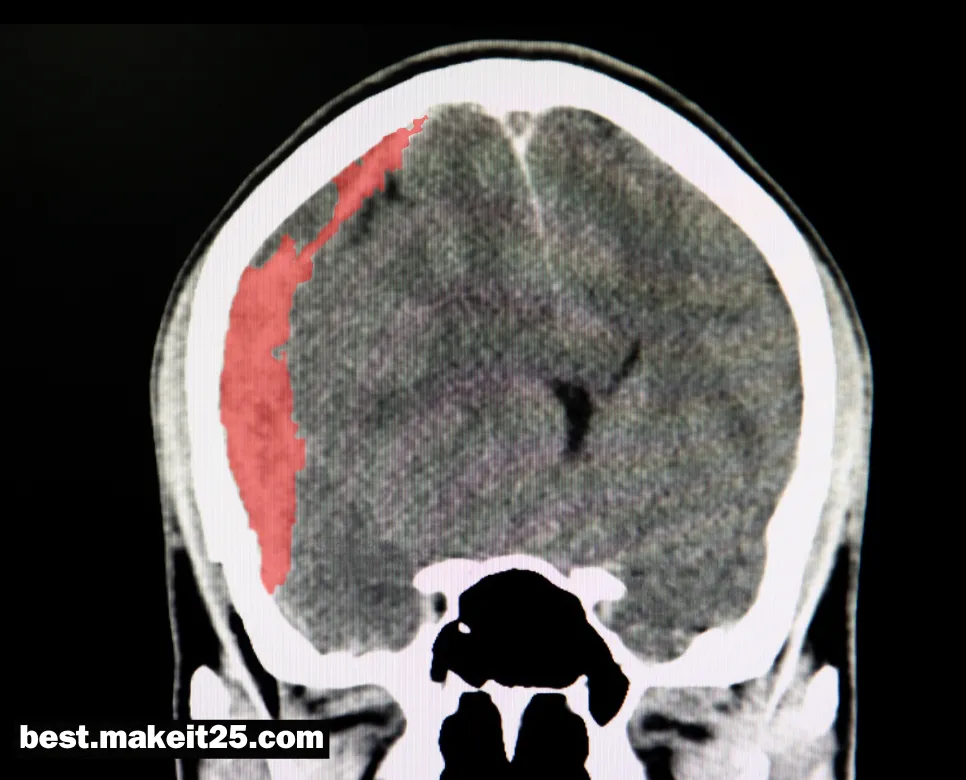

SAH는 의학 용어로 Subarachnoid Hemorrhage의 약자이며, 한글로는 ‘지주막하 출혈’을 의미합니다. 지주막하 출혈은 뇌를 둘러싸고 있는 지주막 공간에 피가 고이는 상태를 말합니다. 대부분의 지주막하 출혈은 뇌동맥류의 파열로 인해 발생하며, 심각한 신경학적 결손과 생명을 위협할 수 있는 응급 상황입니다.

- CT 또는 MRI 영상 검사: 지주막하 공간에 고인 피를 확인할 수 있습니다.

요약하면, SAH는 뇌를 둘러싸고 있는 지주막 공간에 출혈이 발생하는 심각한 질환입니다. 주로 뇌동맥류 파열에 의해 발생하며, 심한 두통, 의식 변화, 구토 등의 증상을 나타냅니다. CT, MRI, 뇌척수액 검사 등을 통해 진단하고, 신경외과적 수술, 뇌압 조절, 발작 예방, 혈관 연축 관리 등의 방법으로 치료합니다. 지주막하 출혈은 신속한 진단과 적절한 치료가 이루어지지 않으면 심각한 후유증이나 사망에 이를 수 있는 응급 질환입니다.